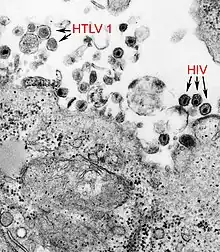

This image revealed the presence of both HTLV-1, and HIV.